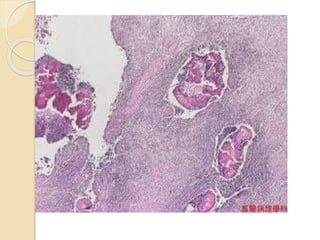

BIOPSY under guideCT Slowly growing gram +ve bacteria : actinomyces israeli

Actinomycosis Actinomyces Slow growing gram+ve bacteria , it is a part of the oral flora in humans, flamentous structure gives them fungal like appearance

Actinomycosis IActinomycosis is infectionis infection caused by actinomyces bacteria Characterized by characteristic granulomatous suppurative disease characterized by peripheral spread with formation of draining sinus affect cervicofacial,thoracic,abdominal,pelvi

Actinomyces in clinicalspecimen sputum .crust purulent exudate surgical nacropsy ,rinsed stain reveal organisms with classic silver granules